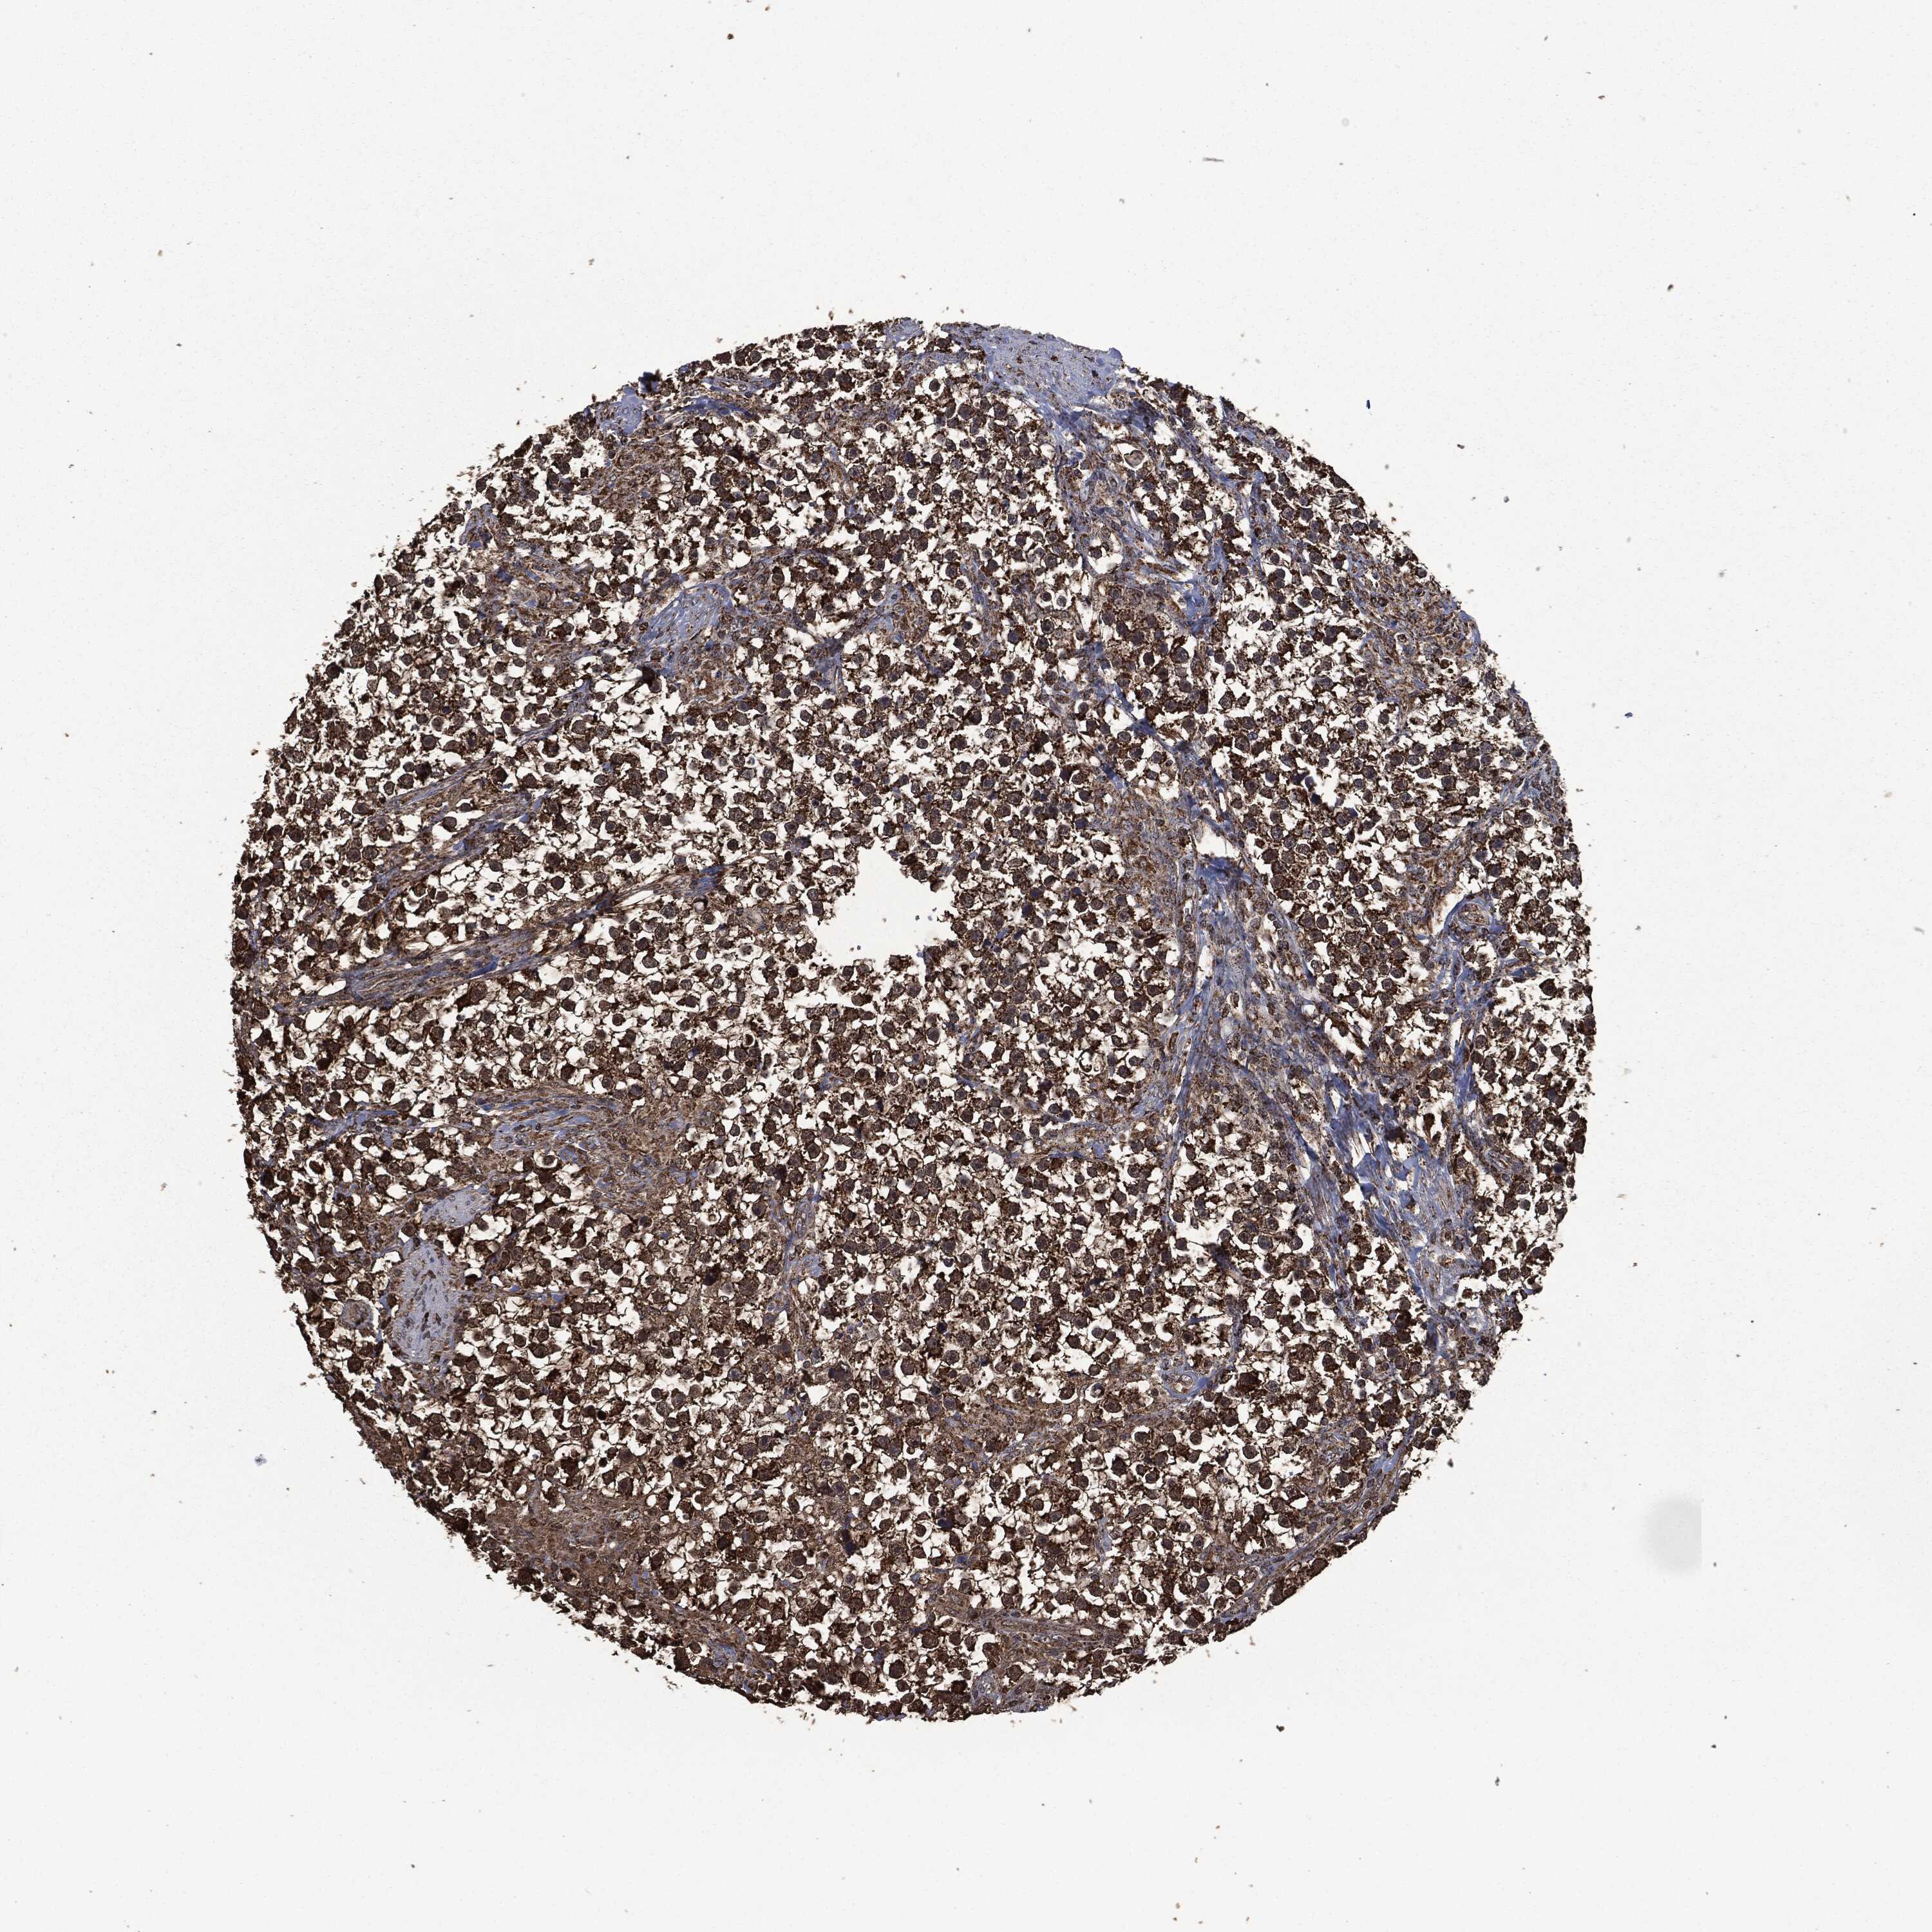

Antibody HPA006723

Staining

High

Medium

Low

Not detected

Intensity

Strong

Moderate

Weak

Negative

Quantity

>75%

75%-25%

<25%

None

Location

Carcinoma, Embryonal, NOS

Seminoma, NOS

TESTIS CANCER - Protein expressioni

A mouse-over function shows sample information and annotation data. Click on an image to view it in a full screen mode. Samples can be filtered based on level of antibody staining by selecting one or several of the following categories: high, medium, low and not detected. The assay and annotation is described here.

Note that samples used for immunohistochemistry by the Human Protein Atlas do not correspond to samples in the TCGA dataset.

Antibody stainingi

Antibody staining in the annotated cell types in the current human tissue is reported as not detected, low, medium, or high, based on conventional immunohistochemistry profiling in selected tissues. This score is based on the combination of the staining intensity and fraction of stained cells.

Each image is clickable and will lead to virtual microscopy that enables deeper exploration of all samples and also displays staining intensity scores, fraction scores and subcellular localization as well as patient and tissue information for each sample.